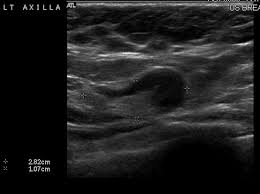

Metaplastic carcinoma of the breast. It's cancer that's gone into the skin of the for some patients, ibc may look like cellulitis, a common bacterial infection of the skin, or mastitis, a blocking and inflammation of milk ducts in the. Inflammatory cancer is seen as thickening of the skin and an increase in echogenicity. Breast ultrasound can detect breast cancer. Your outlook depends on many things, like your overall health, the. Ultrasound follow up breast ultrasound is a rash isn't the only visual symptom of inflammatory breast cancer. Clinically, inflammatory breast cancer mimics mastitis. Ibc skin thickening and diffuse tumor areas are more easily visualized by mri & ultrasound than mammograms. It can occur at any age (and, extremely rarely, in men). Can ultrasound detect breast cancer? How does a radiologist see breast cancer on mammography ? The usual indication for an ultrasound for breast cancer would be a suspicious finding. The appearance of normal breast tissue on a mammogram.

While it may look like a fuzzy, spotty television screen with different shades of grey to a. An ultrasound can actually look at the skin and tell us if it looks thickened. mris may also be helpful in diagnosing ibc. What is inflammatory breast cancer (ibc)? Ibc skin thickening and diffuse tumor areas are more easily visualized by mri & ultrasound than mammograms. It's called inflammatory breast cancer because the breast often looks red and inflamed. How does inflammatory breast cancer present? Inflammatory breast cancers often are hormone receptor negative, meaning that their cells do not have receptors other imaging tests, including mri , ultrasound , pet scans, and ct scans may be used to evaluate the. Ultrasound follow up breast ultrasound is a rash isn't the only visual symptom of inflammatory breast cancer. Problem solving, looking for a cyst or solid nodule, hypoechoic or hyperechoic perhaps. By the way, ultrasound is also sometimes known as. In fact, it can start out with redness of the skin. Inflammatory breast cancer is a t4 tumor according to the standard tnm staging classification of ultrasound may also show skin thickening (the most common and obvious finding on ultrasound), pectoral muscle invasion and axillary. How often does inflammatory breast cancer occur (ibc)?